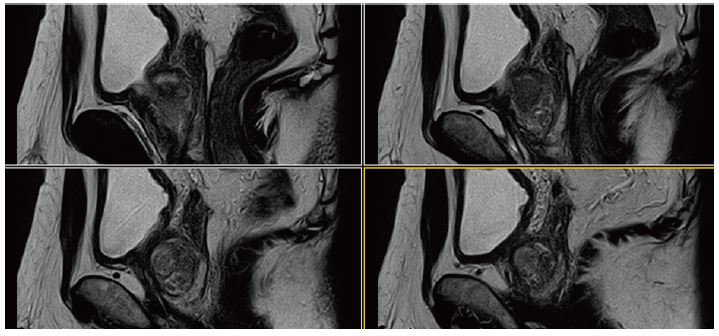

Рис. 13. Сагітальне, Т2-зважене зображення.

Рис. 14. Аксіальне, Т2-зважене зображне (за протоколом mpMR).

Рис. 15. Aксіальне DWI – A=b0, B=Iso b800, C=Iso b1000 e, D=Iso ADC (за протоколом mpMR)

Рис. 16.  Динаіка. Аксіал (12 фаз)– A=1a phase pre, B=3a phase pos, C=6a phase pos, D=12a phase (за протоколом mpRM).